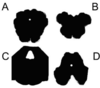

The preganglionic neurons of the sympathetic nervous system are located in this section.

A

B

C

D

The preganglionic neurons of the sympathetic nervous system are located in this section.

A

B

C

D